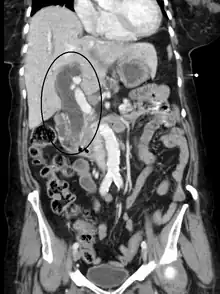

Ces examens sont distingués en non-invasifs et invasifs. Les examens non-invasifs sont utilisés en première intention, dans le but d'évaluer une obstruction des voies biliaires, l'état du foie et du pancréas, l'état vasculaire… Il s'agit de :

- l'échographie abdominale avec doppler.

- IRM abdominale et biliopancréatique.

- Tomodensitométrie abdomino-pelvienne avec injection.

Plus risqués, et selon des indications particulières (nécessité de ponction ou de biopsie ou à visée thérapeutique) sont des examens invasifs tels que l'échoendoscopie et différents types de cholangiographie (en)[12],[14].